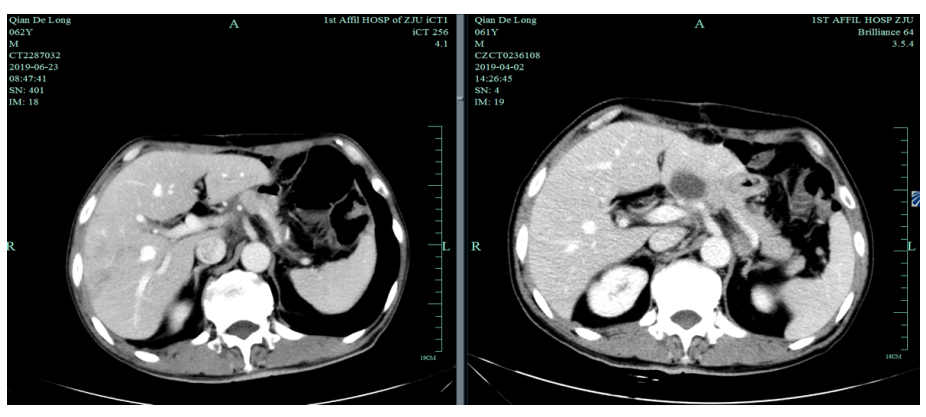

2019-4-2至2019-6-5行SOX+赫赛汀 q3w 4周期联合化疗:具体为奥沙利铂220mgD1、替吉奥3# BID D1-14、赫赛汀400mg(首次)+300mg。

一线化疗疗效评估(2019.6 vs 2019.4):胃癌术后改变。影像评估CR。

入我院后全面进行评估(2019.4):全腹部CT平扫+增强评估提示腹膜后,胰腺周围多发淋巴结增大,淋巴结转移考虑。